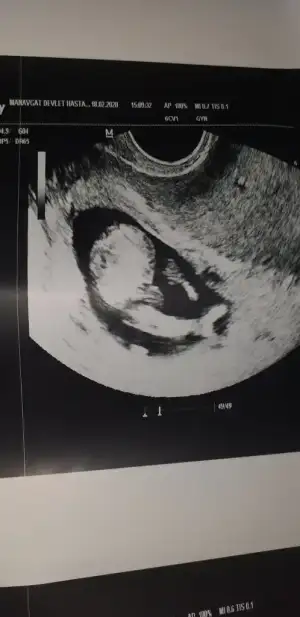

KizEki Görüntüle 2593205 Eki Görüntüle 2593206 Eki Görüntüle 2593208 Eki Görüntüle 2593209 M mely15Ikra meyra bakabilirmisinix bi arkadasın çok merak ediyo

Banada bakarmısınız 12+2 günlükErkek ve kız için 11 yada 12 hafta usg görüntüsü olmalı açıklamalar asagıda yazıyorrabbim herkesin gönlüne göre nasip etsin inşallah .. ecmain

Net değil başka usg paylaşımBanada bakarmısınız 12+2 günlük